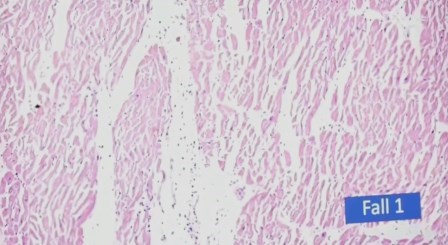

He aquí lo mostrado. Primero, en corazón:

Destrucción de la fibra muscular y el edema

Lo mismo, los puntitos negros que son los linfocitos